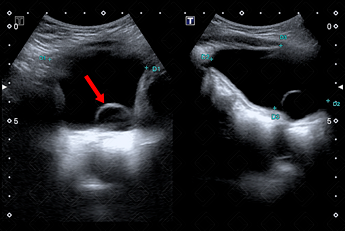

Texto alternativo para a imagem Figura 2. Créditos: Dra. Elazir Mota - Rio de Janeiro/RJ

Descrição da figura 2: Uretrocistografia miccional, estudo durante a fase de enchimento vesical. A ureterocele pode ser visualizada neste exame como falha de enchimento no interior da bexiga (seta amarela).

• Uretrocistografia miccional: Exame de escolha para avaliação e graduação do refluxo vesicoureteral na população pediátrica. A ureterocele pode ser visualizada nesse exame como falha de enchimento no interior da bexiga. Em geral, também melhor visualizada na fase de enchimento vesical (figura 2).